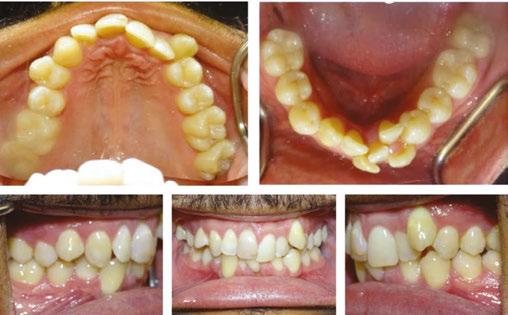

Minor adjustments in torque were then resolved with .016 x .022 NiTi wires placed on June 22, 2022. By October 19, 2022, the patient’s spaces were consolidated, and all teeth were properly leveled and aligned. The finishing stage of treatment (Figure 10) involved minor detailing and Class II elastic wear. The tissue is healthy, spaces are consolidated, the patient is happy with the current esthetic result.

Figure 7: Progress intraoral photos taken on February 10, 2021 Figure 8: Progress intraoral photos taken on April 7, 2021 Figure 9: Progress intraoral photos taken March 3, 2022 Figure 10: Progress extraoral (Figures 9A–9C) and intraoral (Figures 9D–9H) photos taken January 18, 2023 A. A. A. A. D. F. G. H. B. E. C. C. C. C. D. D. D. E. E. E. B. B. B.